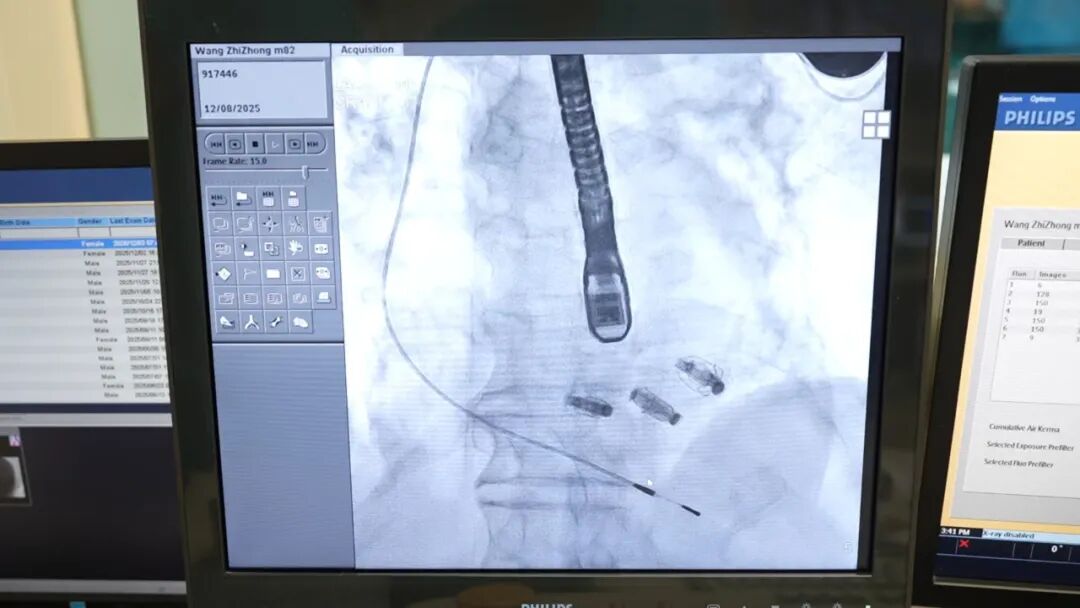

手术当天,袁义强院长、刘煜昊主任、陈同峰博士等专家凭借精湛技术,通过股动脉、股静脉穿刺建立微创通道,将纤细的器械精准送达心脏瓣膜位置。术中,专家团队既要避开起搏器导线的干扰,又要精准定位瓣膜反流靶点,操作难度堪比 “在心脏里穿针引线”。经过数小时的精细操作,成功为患者完成二尖瓣、三尖瓣钳夹修复。